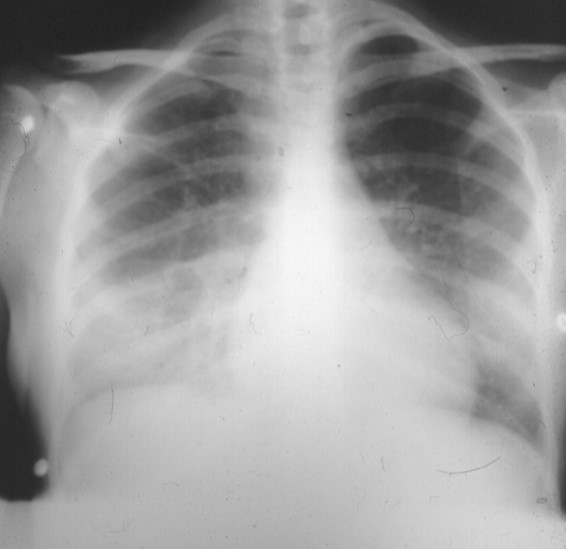

Patient B: A 56-year-old man with paraneoplastic Cushing's Disease who developed fever,

rigors, and progressive dyspnea the night before he was scheduled for an adrenalectomy.

In panels B and C cryptococcal pneumonia was accompanied by cryptococcal fungemia.

Both patients had impaired cell-mediated immunity, in patient B due to his paraneoplastic

Cushings syndrome, and in patient C due to her chemotherapy-induced leukopenia. These

patients received intravenous amphotericin B but, unfortunately, both expired despite

treatment.

Lingular segment C. neoformans Left upper lobe C. neoformans pneumonia in a patient pneumonia in a normal host. with paraneoplastic Cushings syndrome.